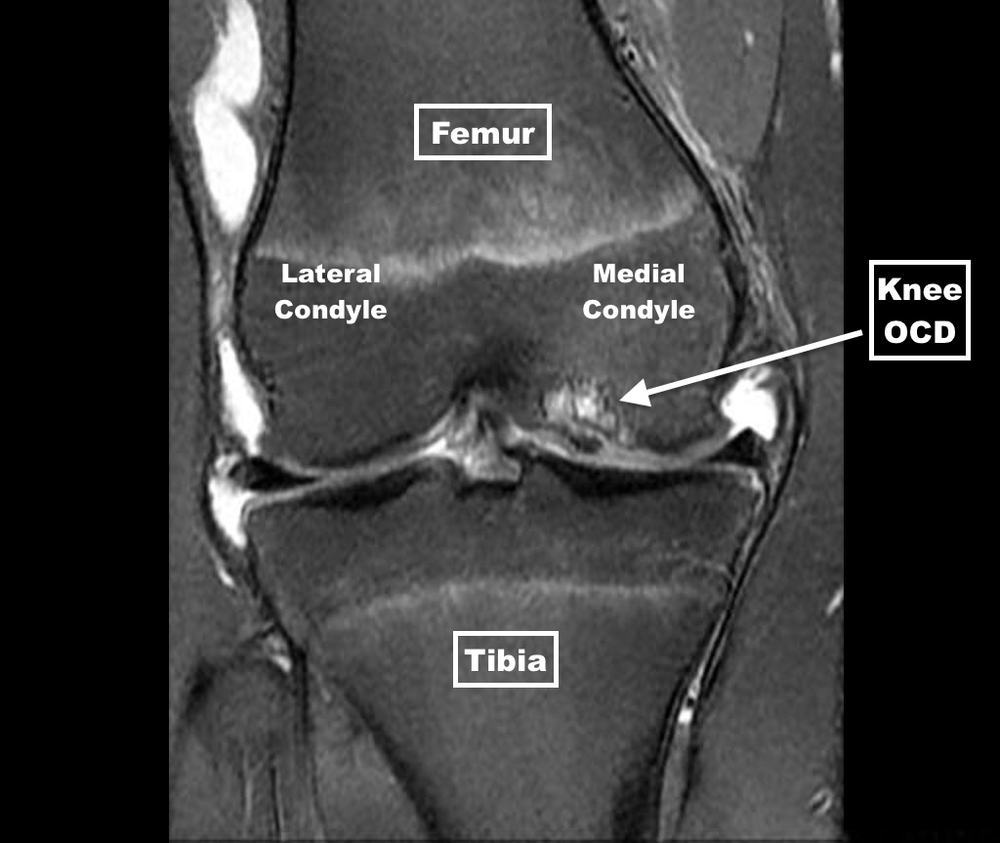

From www.theinjurysource.com

Osteochondritis Dissecans of the Knee Osteochondritis Dissecans Knee Brace osteochondritis dissecans of the knee (ocd) is a multifactorial pathology in where repetitive microtrauma plays a. the purpose of this manuscript is to analyze the evidence regarding etiopathogenesis of knee osteochondritis. osteochondritis dissecans (ocd) is a disorder resulting in focal breakdown of the subchondral bone, with. osteochondritis dissecans is a pathologic lesion affecting articular cartilage and. Osteochondritis Dissecans Knee Brace.